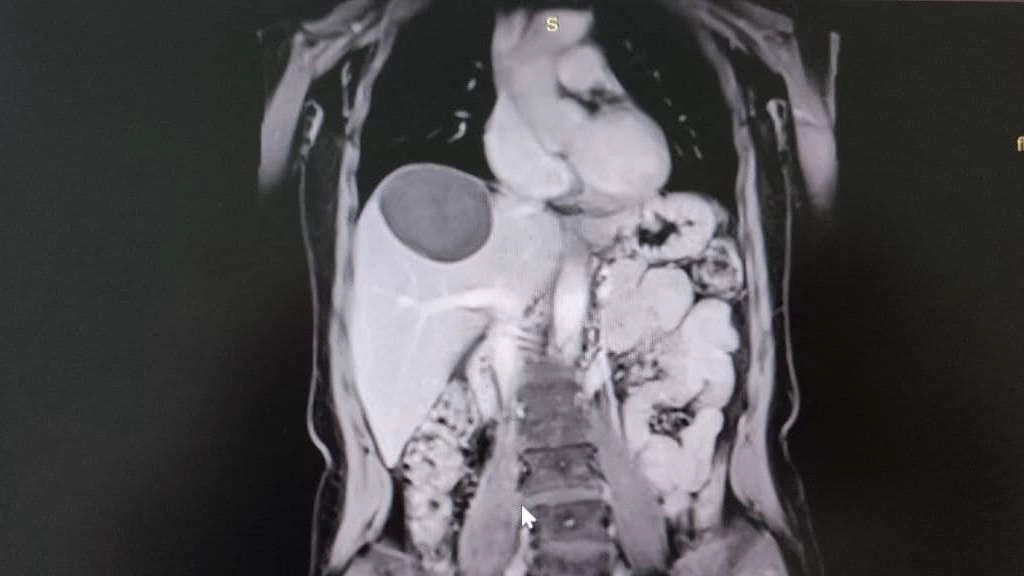

Хірурги Володимирського ТМО видалили гігантський жовчний міхур у пацієнта. Про це повідомляють на сторінці Володимирського ТМО у фейсбуці. "Не боїмося складних випадів! Хірурги Володимирського територіального медичного об'єднання видалили жовчний міхур величезних розмірів", - йдеться у дописі володимирських медиків. ...